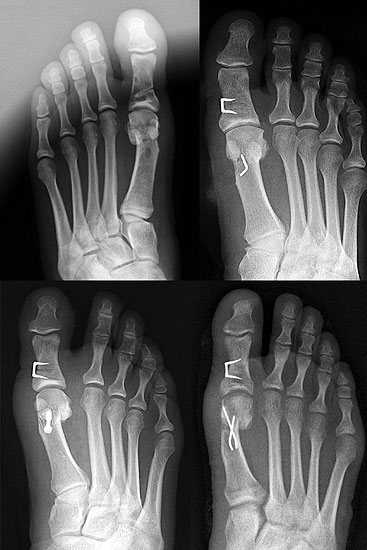

Abbildung 1

Klinische Untersuchung des gesamten Fußes unter Entlastung und Belastung

Röntgenaufnahmen des Fußes d.p., streng seitlich und schräg unter Belastung

Operationsplanung anhand der Röntgenaufnahmen unter Beachtung wichtiger radiologischer Landmarks wie Intermetatarsalwinkel, Hallux valgus – Winkel, Distaler Gelenkflächenwinkel (Distal metatarsal articular angulation: DMAA), Metatarsaleindex und Sesambeinposition (Abbildung 1)

Die Chevron Osteotomie ist eine der weltweit am häufigsten angewandten Verfahren zur Korrektur einer milden bis mittelgradigen Valgusfehlstellung der Großzehe 1110121319148. Die zahlreichen Publikationen berichten über relativ verlässlich gute und reproduzierbare Ergebnisse. Durch Modifikationen in der Operationstechnik versuchten einige Autoren den Indikationsbereich auf mittelgradige bis schwerwiegende Fehlstellungen auszuweiten 121314. Die Bestimmung des Schweregrades der Fehlstellung erfolgt in erster Linie am belasteten Röntgenbild im dorsoplantaren Stahlengang (siehe Abbildung 1). An dieser Aufnahme können die wichtigsten radiologischen Vermessungen zur Operationsplanung vollzogen werden 112310121312728172930, auch wenn in einigen Studien eine große inter- und intraindividuelle Schwankungsbreite der Messergebisse dargestellt werden konnte 2930. Ebenso zeigt sich eine gewisse Varianz in der Methodik zur Bestimmung des ersten Intermetatarsalwinkels 18282931. Als Grenzwerte für einen milden bis mittelgradigen Hallux valgus werden in der Literatur in relativ weiter Übereinstimmung ein Intermetatarsalwinkel bis maximal 16° und ein Hallux valgus Winkel bis 40° genannt 688. Der DMAA ist radiologisch schwierig zu beurteilen und sollte intraoperativ bei Gelenkeröffnung inspektorisch überprüft werden 2. 2007 verglichen Trnka et al. (2007) die Ergebnisse von vier verschiedenen Nachuntersuchungsgruppen, die sich durch Modifikationen der OP Technik unterschieden: 66 Chevron Operationen von 1991 bis 1992, 100 Chevron Operationen von 1992 bis 1995, 55 Chevron Operationen von 1994 bis 1995 und 89 Chevron Operationen von 2000 bis 2002. So wurde der dorsomediale Zugang 1992 durch einen streng medialen Zugang mit L-förmiger Kapsulotomie ersetzt. 1992 wurde das laterale Release über einen dorsalen Zugang eingeführt mit Perforation der lateralen Kapsel längs zwischen Metatarsale 1 und fibularem Sesambein, sowie vertikal im Verlauf der Gelenklinie ohne Ablösung des Adduktors oder Durchtrennung des intermetatarsalen Bandes. Zwischen 1994 und 2000 wurde eine temporäre Fixation mit einem Kirschnerdraht durchgeführt. Seit 2000 wird die Osteotomie mit einer kanülierten Kompressionsschraube fixiert. Insbesondere die Einführung des lateralen Release führte zu einer signifikanten Verbesserung des Hallux valgus- und Intermetatarsalwinkels, ohne vermehrt Probleme mit einer avaskulären Nekrose des MTK 1 zu bekommen. Die Einführung einer Osteosynthese mittels Kirschnerdraht zeigte im follow up nach 34 Monaten gegenüber der lediglich manuellen Einstauchung des distalen Fragments, wie in der Originalarbeit von Austin beschrieben, eine geringere Rate an Korrekturverlusten und Dislokationen des ersten Metatarsaleköpfchens. Durch die Verwendung einer Schraube konnte das Indikationsspektrum hinsichtlich Schweregrad des Hallux valgus erweitert werden. Der Vergleich einer 2-Jahres- und eines 5-Jahres-Nachuntersuchung zeigte gegenüber der präoperativen Untersuchung eine Verbesserung des IM-Winkels von 13° auf 8° respektive 9°. Der HV-Winkel konnte von durchschnittlich 29° auf 15° respektive 16° reduziert werden. Ergebnisse, welche auch die langfristige Zuverlässigkeit der Chevron-Osteotomie in der Behandlung des milden bis mittelgradigen Hallux valgus belegen.